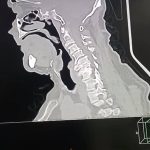

حيث استقبل المستشفى مريضًا يبلغ من العمر 70 عامًا، كان يعاني من ضعف تام وشلل كامل بالأطراف الأربعة، مع فقدان شبه كامل للتحكم في البول والبراز، وذلك على خلفية ادعاء التعرض للسقوط. وبإجراء الفحوصات الطبية والأشعات اللازمة، تبين إصابة المريض بانزلاق غضروفي عنقي متعدد على أربعة مستويات،

ما أدى إلى حدوث كدمة بالحبل الشوكي وضيق كامل بالقناة الشوكية العنقية، وهي من الحالات شديدة الخطورة التي تستدعي تدخلاً جراحيًا دقيقًا وعاجلًا.

وعلى الفور تم تجهيز الحالة طبيًا من خلال إجراء جميع الفحوصات والتحاليل اللازمة، قبل أن يخضع المريض لجراحة ميكروسكوبية دقيقة ومعقدة، تم خلالها استئصال الغضاريف المنزلقـة، وتركيب أقفاص عنقية مثبتة بدعامات ذاتية (Stand-alone) على أربعة مستويات، وذلك باحترافية عالية، مع خروج المريض من غرفة العمليات في حالة مستقرة وآمنة.